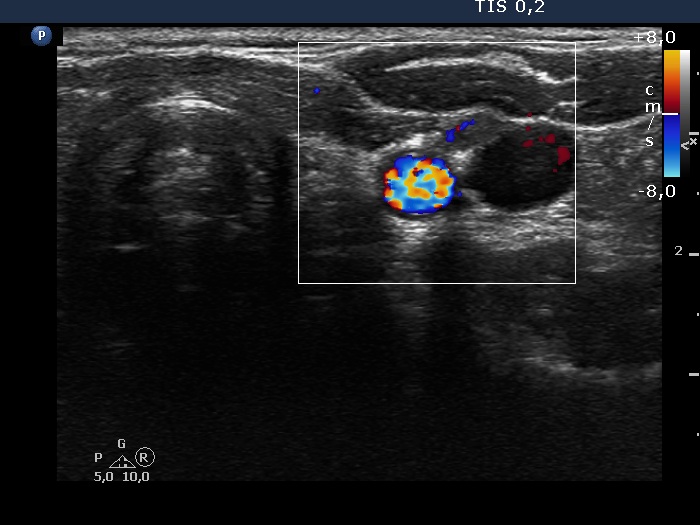

Follow-up investigation two years later (ultrasonographic picture 9)

Left lobe and lateral to the left lobe, transverse scan, color Doppler mode. The scanty vascularity proves that the mass is not a muscle fiber.